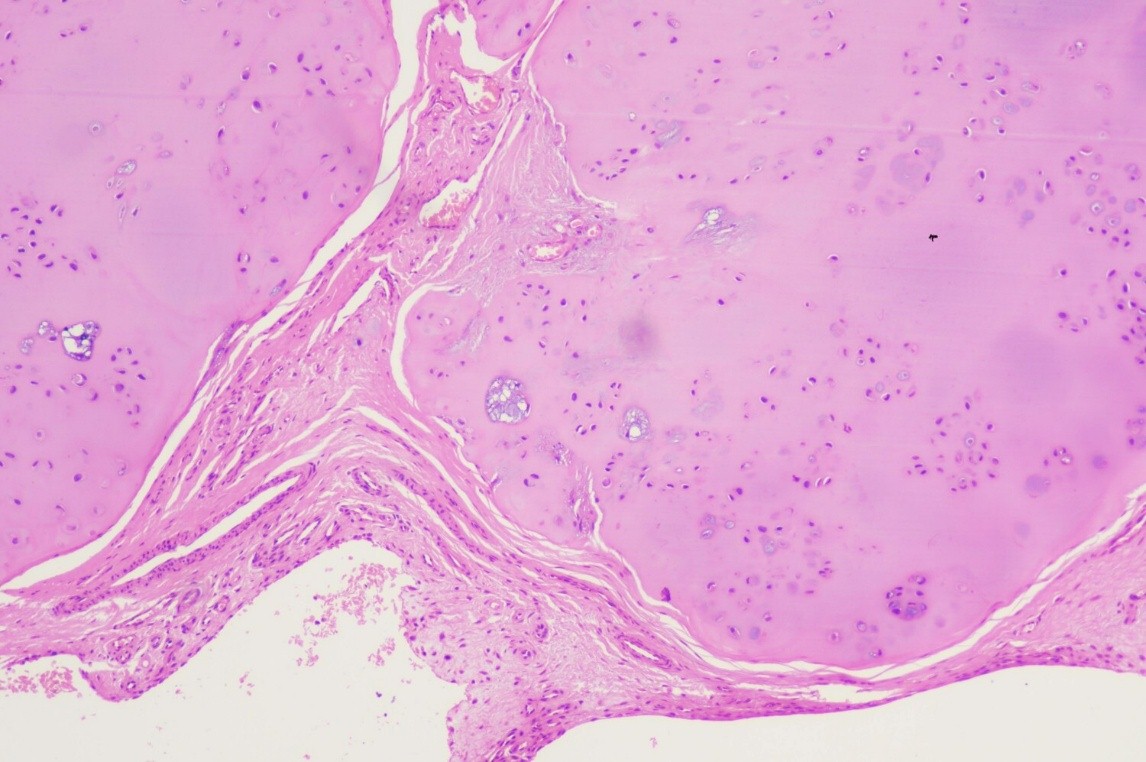

After detailed counseling regarding the nature of the lesion and treatment options, the patient consented to surgical intervention. A surgical approach was planned, and an open excisional biopsy was performed using a posterior reverse L-shaped incision (Burks-Schaffer approach) [7]. On posterior capsule opening, a 2.5 cm × 2.5 cm encapsulated mass was identified behind the PCL and was excised en bloc. The mass contained multiple white loose bodies, each approximately 5 mm in diameter (Fig. 3). Both the excised loose bodies and synovial tissue were sent for histopathological analysis. Histopathological examination identified nodules of hyaline cartilage with clustered chondrocytes, encased by synovial tissue of varying thickness, thereby confirming the diagnosis of SC (Fig. 4).

Figure 4: Histological section demonstrating nodules of hyaline cartilage with clustered chondrocytes, surrounded by synovial tissue of variable thickness, consistent with synovial chondromatosis (H&E stain, ×10).